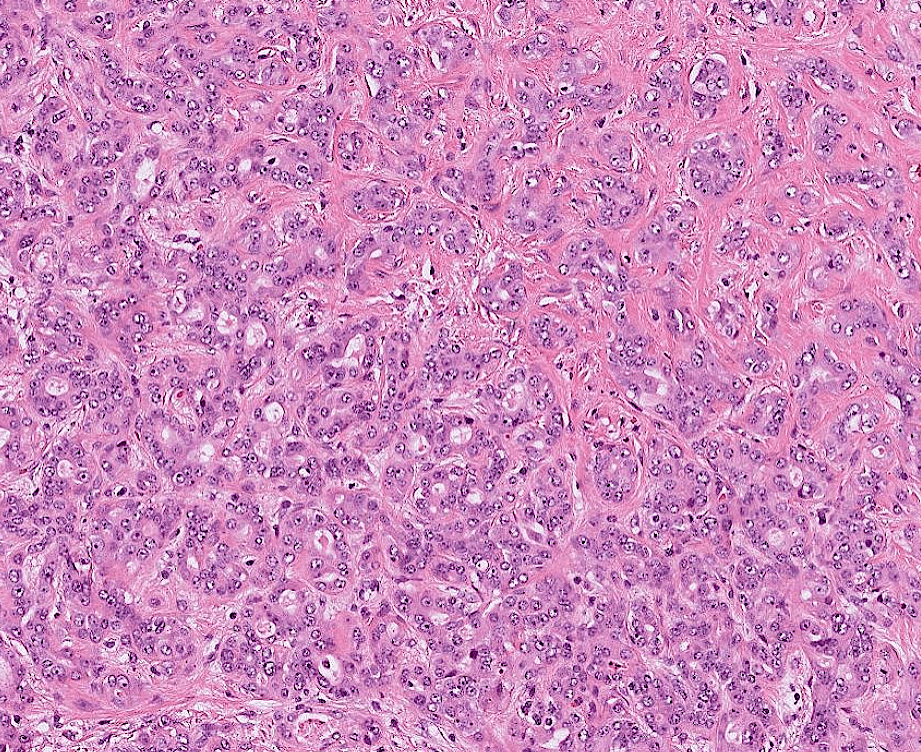

endometrial cancer